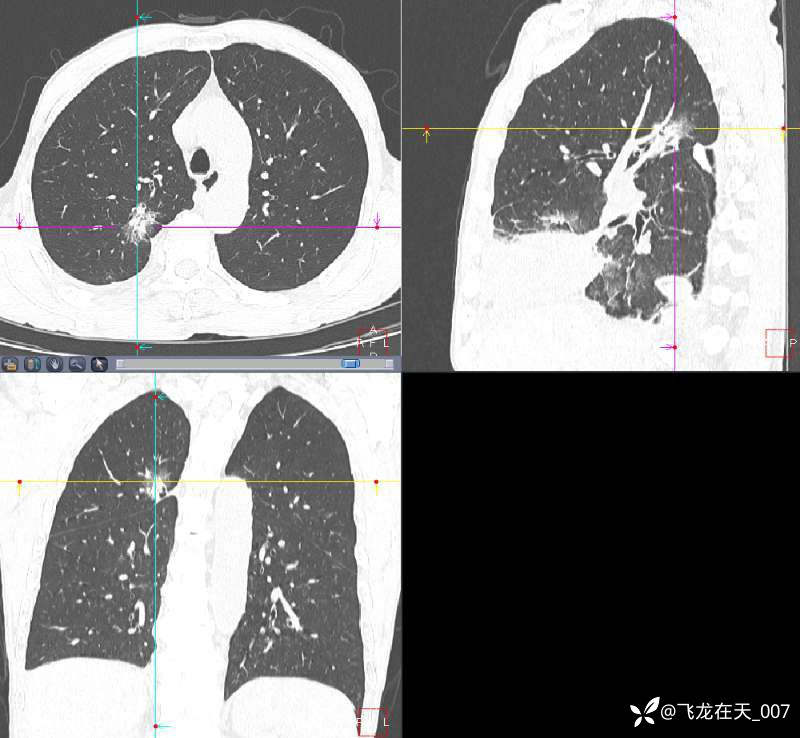

主诉:发现肺部结节3年余,胸痛半月余

现病史:患者自诉3年余前体检发现右肺上叶结节,未予特殊诊治,后定期复查。半月余前患者无明显诱因下出现胸痛、咳嗽,伴活动后胸闷、气喘不适,无明显咳痰、咯血、发热,胸部CT检查提示右肺上叶部分实性结节,较前增大。既往无特殊病史。

胸部CT检查图像如下: